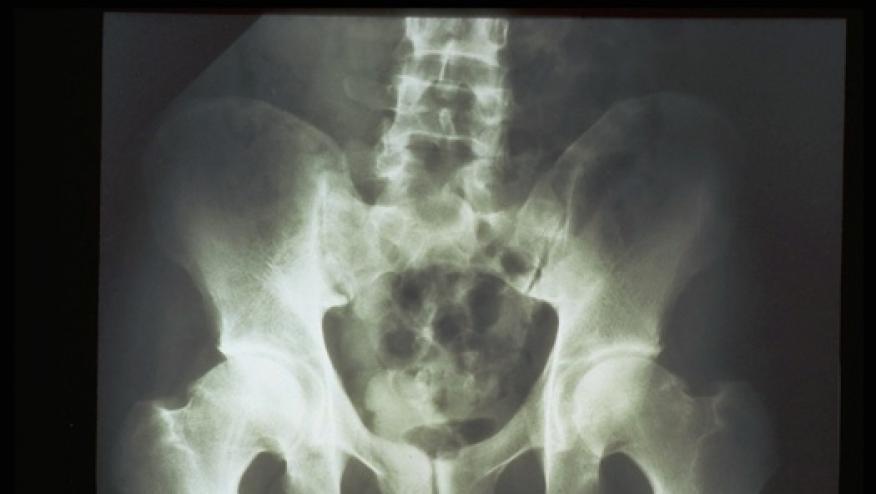

Most patients with early, active axial spondyloarthritis (axSpA) who quickly received a tumor necrosis factor (TNF) inhibitor experienced remission, and it didn't matter whether or not they had intestinal inflammation at baseline, a small single-arm study found.

Sustained clinical remission while receiving golimumab (Simponi) was achieved by 61.8% of 58 patients in the trial, and the rate didn't differ significantly with respect to gut inflammation status (OR 1.50, 95% CI 0.39-6.49), according to Dirk Elewaut, MD, PhD, of Ghent University in Belgium, and colleagues.